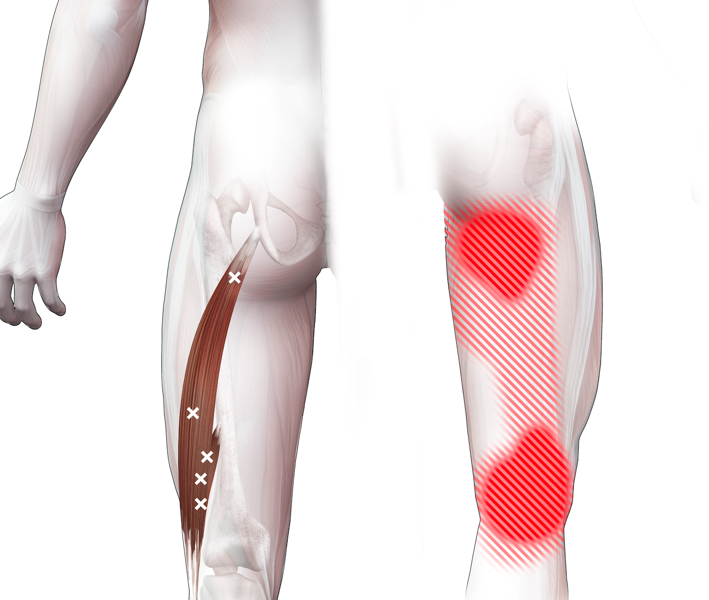

Klachtgebied

Klachten

klachten

Spieren (Nederlands)

Spieren (nederlands)

Spieren (Latijn)

Spieren (latijn)

Trefwoorden

Trefwoorden